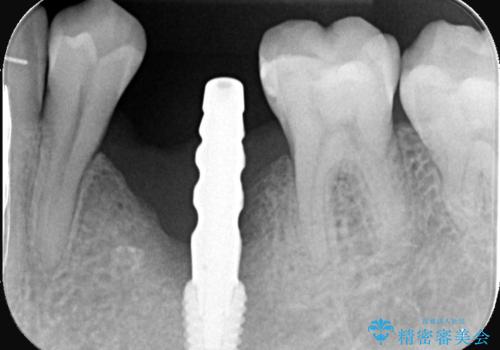

インプラントを抜去後、再びインプラントで治療を行いました。

当法人はどんなインプラントでも簡単に除去する事ができ、痛みが少なくインプラントを埋入する事ができます。

当患者様もインプラントのオペ後痛みが全くなく痛み止めも1錠も飲まず驚かれていました。